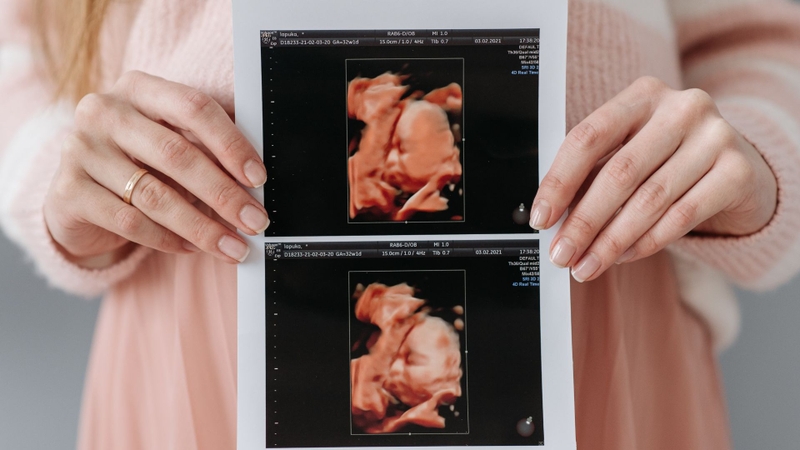

Siêu âm ở tuần 18 là một bước kiểm tra quan trọng để đánh giá sự phát triển của thai nhi và phát hiện sớm các bất thường nếu có. Đây cũng là dịp để mẹ nhìn thấy bé yêu rõ hơn qua màn hình siêu âm. Đồng thời, bác sĩ có thể kiểm tra một số thông tin cơ bản sau:

Mặt khác, chuyên gia sẽ đánh giá những chỉ số siêu âm quan trọng phản ánh sự phát triển khỏe mạnh của bé, bao gồm:

Những chỉ số này giúp bác sĩ đánh giá xem thai nhi có phát triển đúng chuẩn hay không. Nếu có bất kỳ dấu hiệu bất thường nào, bác sĩ sẽ tư vấn thêm để mẹ có hướng xử lý kịp thời.